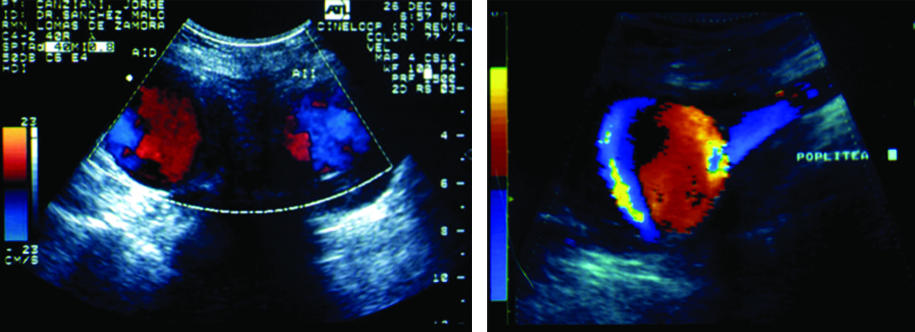

Pseudo-aneurisma

Complicación tardía de las anastomosis de los bypass, también pueden presentarse por traumatismo en la anastomosis, como se observa en la imagen (Fig. 24).

PSEUDO-ANEURISMAS

Se producen como complicación de una instrumentación quirúrgica o por heridas de armas de fuego o de armas blancas. La efracción del vaso determina la salida de sangre hacia los tejidos blandos, los cuales reaccionan formando una capsula (Fig. 47).

A diferencia de los aneurismas verdaderos, los pseudo-aneurismas no presentan los tres componentes de la pared y se encuentran recubiertos por tejido de granulación, y su topografía es más frecuente la arteria femoral común. La frecuencia de aparición en los procedimientos percutáneos vasculares es de 0,5 a 1%. La compresión extrínseca del pseudo-aneurisma es la primera línea de tratamiento (Fig. 48 y 49).